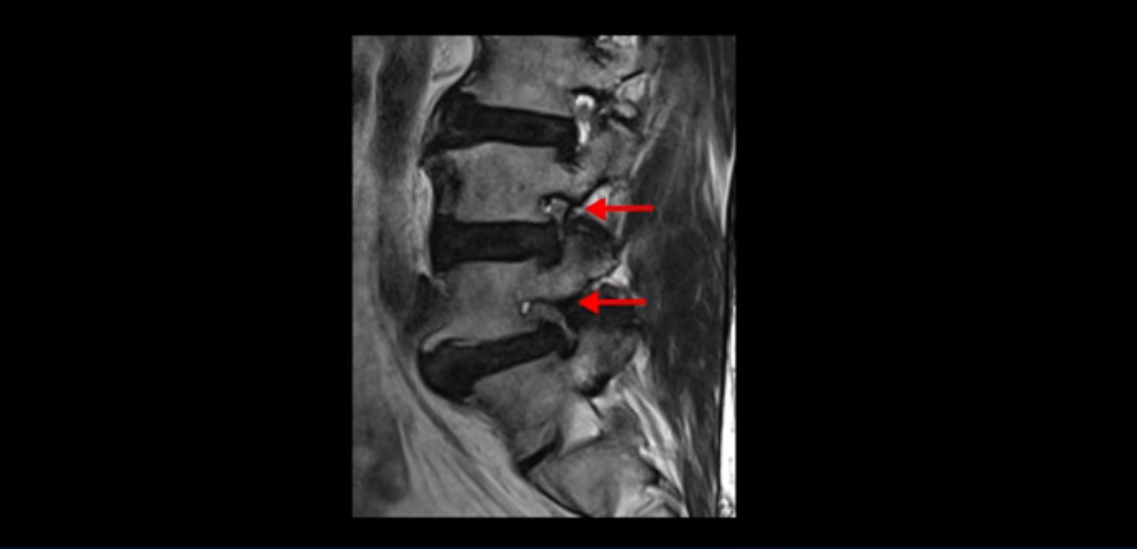

이 환자분은 협착증 수술을 두 번 받은 뒤에 또 다시 다리 방사통이 심해지고 발목 마비 증상(풋드랍)이 생겨서 이번에는 유합술을 권유받은 환자분입니다. 먼저 MRI를 보고 설명해 드린 후 이런 환자분의 방사통과 발목의 마비와 힘 빠짐이 어떻게 수술 없이도 좋아질 수 있는지 그리고 치료는 어떻게 하는지 자세히 설명드리겠습니다.

이분은 허리 다섯 마디 중 4번 5번, 5번 1번에 감압술로 눌린 신경을 풀어주는 수술을 받았습니다.

후관절을 떼어낸 흔적이 보입니다.

단면으로 보면 왼쪽 후궁을 제거한 흔적이 보입니다.

5번 1번도 왼쪽 후궁을 열고 수술 받았습니다.

하지만 중심성 협착은 여전히 심한 상태입니다.

이분은 오른쪽, 왼쪽 다리에 모두 방사통이 심하고 왼쪽 다리에 마비 증상, 즉 풋드랍(족하수) 증상이 있습니다. 왼쪽 신경 가지가 빠져나가는 추간공을 보면 두 마디가 좁아져 있습니다.

이런 신경 구멍이 좁아져 있는 걸 협착이라고 합니다.

이미 앞선 두 번의 수술로 뼈와 인대 등을 일부 제거해서 안정성이 떨어진 상태에서 추가로 수술하려니까 척추가 너무 불안정해져 무너질 게 걱정되니까 이번에는 나사 박는 유합술을 권유 받은 겁니다. 이런 환자분들의 방사통과 마비 증상이 어떻게 수술 없이 좋아질 수 있을까요? 치료는 어떻게 하는 걸까요?